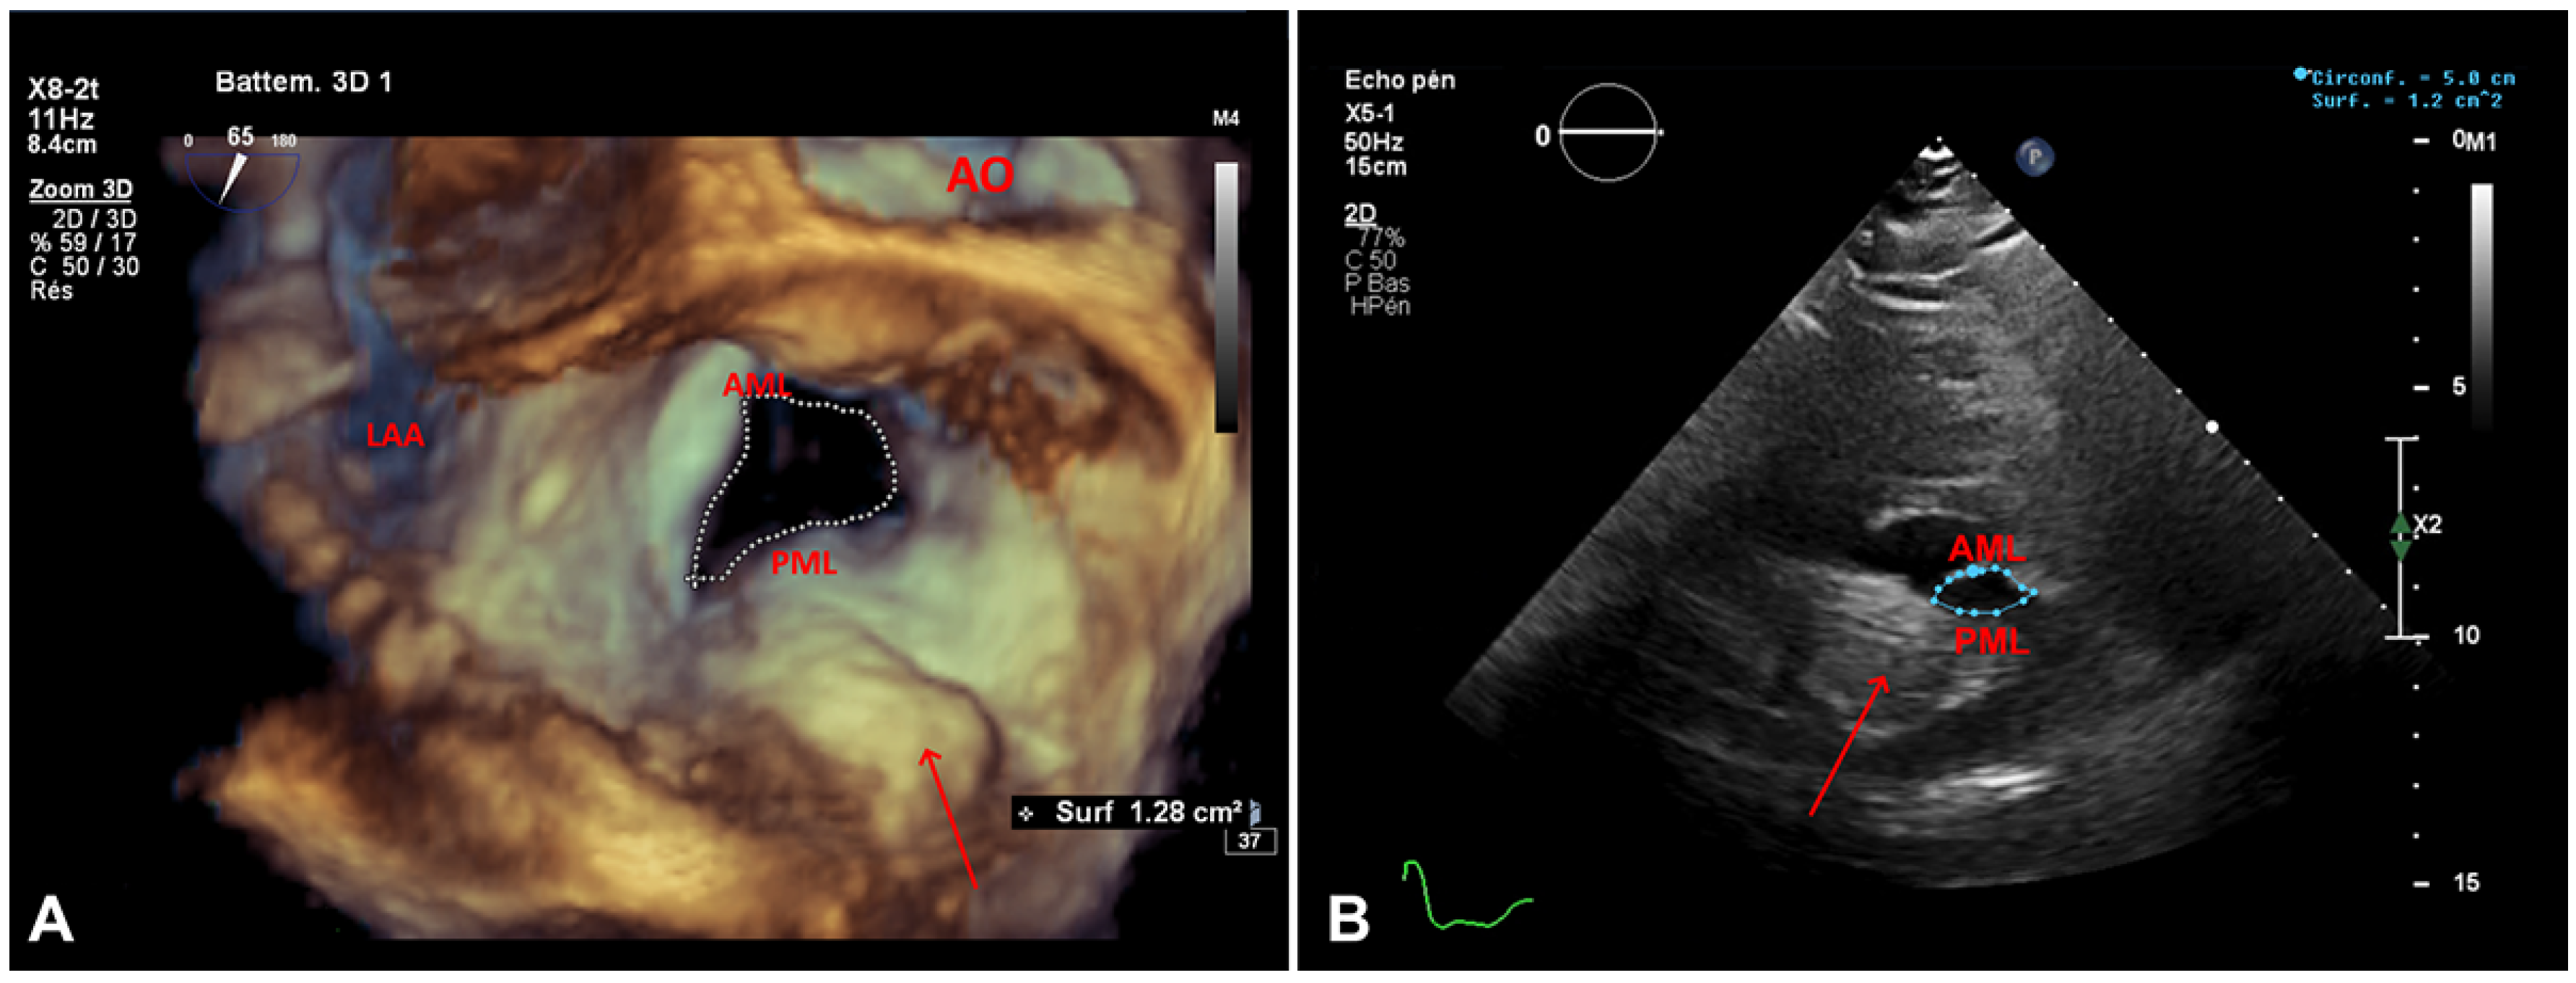

Figure 3. A. Transoesophageal echocardiogram, three-dimensional planimetry of the mitral valve orifice (surgical view) and the (arrow). PML: posterior mitral leaflet; AML: anterior mitral leaflet, AO: aortic valve, LAA: left atrial appendage. B. Transthoracic echocardiogram, two-dimensional planimetry of the mitral valve orifice on parsternal short axis view and the c(arrow). PML: posterior mitral leaflet: AM anterior mitral leaflet.

In the emergency department the patient’s vital signs (oxygen saturation 88%), clinical examination (tachypnoea, orthopnoea, bilateral lung crackles), laboratory tests (elevated N-terminal pro-B-type natriuretic peptide [NT-proBNP]) and chest X-ray (lung congestion) confirmed the diagnosis of acute heart failure, albeit of unclear aetiology: her blood pressure was only mildly increased, mild troponin elevation argued against an acute coronary syndrome, haemoglobin levels and heart rate were stable (Table 1). The patient was admitted for oxygen supplementation and intravenous diuretics with rapid recovery ensuing in a few days. A TTE documented normal heart function but an increase in the size of the cardiac mass ( 46 mm × 31 mm compared with 36 mm × 27 mm 4 years before), the mean gradient across the mitral valve was unchanged at 6–7 mm Hg at a heart rate of 65 bpm (Figure 2) The mitral valve area obtained by two-dimensional planimetry from the parasternal short axis view was 1.2 cm2 (Figure 3B). No other significant valve disease was found. Transoesophageal echocardiography (TOE) showed moderate mitral stenosis. The mitral valve orifice measured by three-dimensional planimetry was 1.4 cm2 (Figure 3A). Remarkably, there was an increase in the mean diastolic mitral gradient from 6 mm Hg at the time of the TTE to 13 mm Hg on TOE, probably due to a higher heart rate of 85 bpm (Figure 5). A CT scan showed an increased size of the mass (Figure 4). Due to the frailty of the patient and in accordance with her wish not to undergo any invasive treatment, surgery was not proposed. The patient was discharged before being admitted 2 months later for another episode of acute heart failure treated with intravenous diuretics. The therapeutic attitude was altered and at this time the patient was again discharged for ambulatory follow up for treatment adjustment and only symptomatic management if acute heart failure happens again.